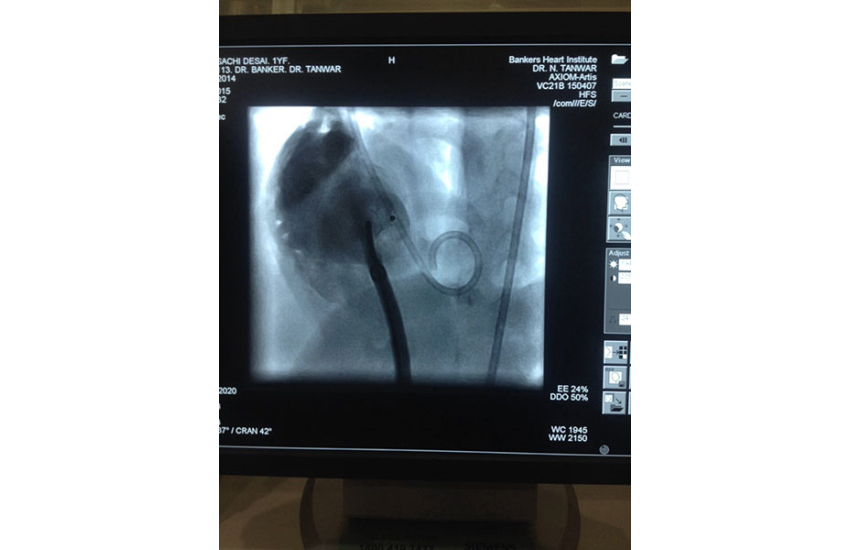

1 year girl with 7 kg weight successfully undergone Ventricular Septal Defect device closure...

18 Sep 2015